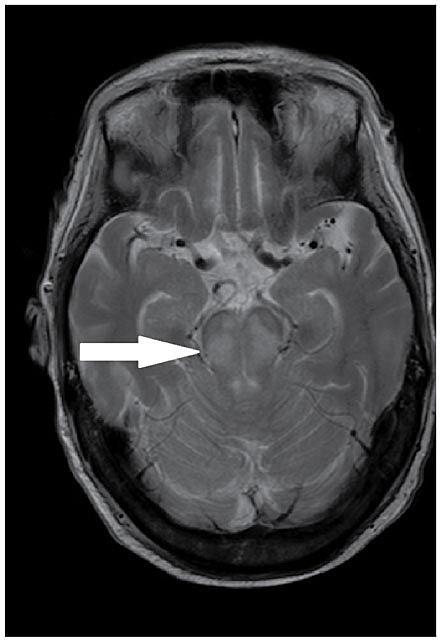

En 84-årig mand blev indlagt på en intensivafdeling med pneumoni og septisk shock. Patienten havde ikke nyreinsufficiens. De første døgn blev han resusciteret med store mængder Na-holdige væsker. Efter to uger var hans tilstand stabil. Han var svært ødematøs, og vægten var 12 kg over den præmorbide. Fra dag 17 steg S-Na-koncentrationen hurtigt (Tabel 1), og patienten fik nonoligurisk nyreinsufficiens med høj S-karbamid- og lav urin-Na-koncentration. På trods af behandling med hypotone væsker og daglig positiv væskebalance steg S-Na-koncentrationen til 165 mmol/l. Patienten blev komatøs og fik myoklonier. Man påbegyndte derfor kontinuerlig veno-venøs hæmodialyse (CVVHD) på dag 21. Blodflow var 125-150 ml/min, og dialysatflow var 2.000-2.500 ml/t. Der blev tilsat ekstra Na til dialysatet, således at gradienten mellem blod og dialysat var 5-10 mmol. Efter 12 timer var S-Na-koncentrationen faldet til 157 mmol/l. Efter yderligere tre dage med CVVHD 12 timer dagligt var S-Na-koncentrationen normaliseret. Patienten var vågen, cerebralt intakt, og myoklonierne var væk. S-Na-koncentrationen forblev i normalområdet, og nyrefunktionen rettede sig langsomt.